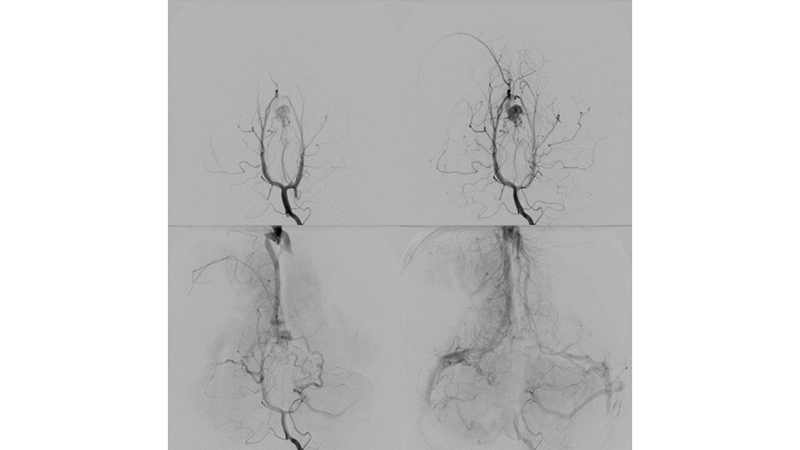

- Προσθιοπίσθια λήψη κατά την έγχυση στην δεξιά έσω καρωτίδα. Η αρτηριοφλεβώδης επικοινωνία της φλέβας του Γαληνού σκιαγραφείται από παλινδρόμηση στην δεξιά υποκλείδιο και σπονδυλική αρτηρία. Η φλεβική παροχέτευση του δεξιού εγκεφαλικού ημισφαιρίου γίνεται πολύ καθυστερημένα, λόγω απόφραξης των εγκαρσίων κόλπων αμφοτερόπλευρα (μαύρα βέλη).

- Προσθιοπίσθια λήψη κατά την έγχυση στην αριστερή έσω καρωτίδα. Η αρτηριοφλεβώδης επικοινωνία της φλέβας του Γαληνού σκιαγραφείται από την οπίσθια αναστομωτική αρτηρία. Η φλεβική παροχέτευση του αριστερού εγκεφαλικού ημισφαιρίου γίνεται πολύ καθυστερημένα, λόγω απόφραξης των εγκαρσίων κόλπων αμφοτερόπλευρα (μαύρα βέλη).

- Προσθιοπίσθια λήψη κατά την έγχυση στην αριστερή σπονδυλική αρτηρία. Ελέγχονται πολλαπλές μικροφίστουλες στο τοίχωμα της φλέβας του Γαληνού και μικρές αρτηριοφλεβώδεις επικοινωνίες στην χοριοειδή σχισμή (μικτού τύπου, τοιχωματικού και χοριοειδούς). Αρδεύονται από υποεπενδυματικούς τροφοφόρους κλάδους, εκ του Ρ1 τμήματος των οπισθίων εγκεφαλικών αρτηριών αμφοτερόπλευρα κυρίως δεξιά, που πορευόμενοι στο πλάγιο τοίχωμα της 3ης κοιλίας εκατέρωθεν, συναντούν την χοριοειδή σχισμή και εκείθεν αρδεύουν την αρτηριοφλεβώδη επικοινωνία (μαύρα βέλη). Επίσης συμμετέχουν οπισθιοπλάγιοι έσω χοριοειδείς (διακεκομμένο κόκκινο βέλος) και οπισθιοπλάγιοι έξω χοριοειδείς κλάδοι (κόκκινο βέλος) από το Ρ2 και Ρ3 τμήματα των οπισθίων εγκεφαλικών αρτηριών αμφοτερόπλευρα, που δια της χοριοειδούς σχισμής καταλήγουν στο οπίσθιο τοίχωμα της φλέβας του Γαληνού. Διακρίνεται επίσης η απόφραξη των εγκαρσίων κόλπων και η αναστροφή της ροής προς το εγκεφαλικό φλεβικό δίκτυο με συμφόρηση των εγκεφαλικών φλεβών.